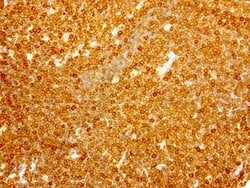

| Immunocytochemistry, Immunofluorescence, Immunohistochemistry (Paraffin) | |